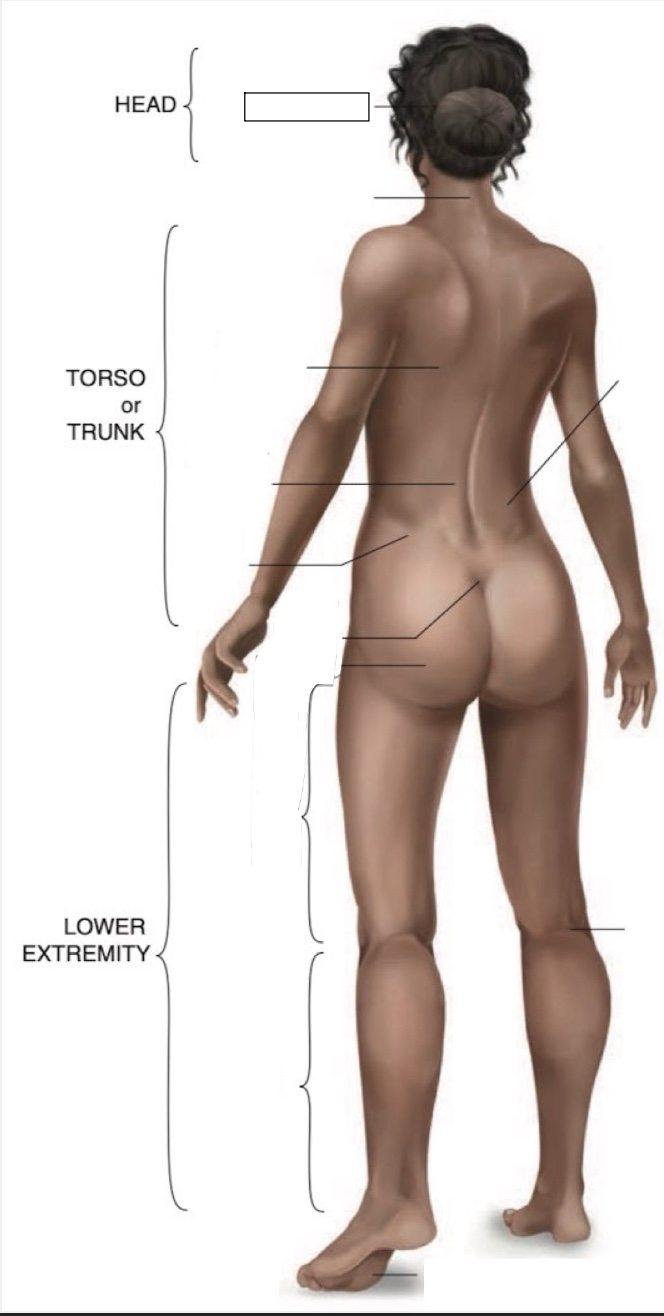

Occipital region

Cervical region

Inferior angle of scapula

Lumbar region

Iliac crest

Sacral region

Buttock

Flank